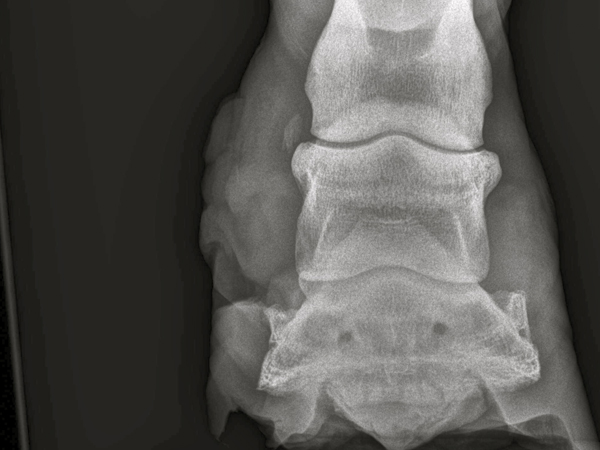

Es war tatsächlich nicht leer. Danach wurde es reichlich desinfiziert und wieder gut Verbunden. danach wurden RTG Bilder gemacht. Es hat sich bestätigt das es sich um einen Fistel handelt. Hufknorpel und Co. wurden aber nicht betroffen.

Tiermedizinisch wurde eingelenkt und ein medikamentöser Schutz eingeleitet. So konnte man aber den „demolierten“ Huf nicht ohne eines mechanischen Schutzes lassen. Eigentlich erinnerte der Huf zu diesem Zeitpunkt eher einer Klaue als einem Huf.

Nach etwa drei Wochen bekam das Pferd einen Klebebeschlag. Damit es nicht so einfach wäre, war es eine Sonderanfertigung.

Ein Renegade Klebebeschlag dank einer recht stabilen geschlossenen Sohle bot genug vertikalen Stabilität.

Es blieb aber noch das Problem des horizontalen Hufmechanismus. Die Hufkapsel bestand zu diesem Zeitpunkt aus zwei Teilen. Das heisst: kein Klebebeschlag soll diese Wand so stabilisieren das sie sich nur wenig bewegt. Man darf nicht vergessen, dass die offene Stelle, wo sich noch bis vor kurzem der Abszessherd befunden hat, nicht stabilisiert (evtl. mit Kunsthorn Ausgefüllt) werden konnte.

Dafür nahm ich eine breitere Schalle des Klebebeschlages als der Huf es war, die ich lateral hervorstehen lies. In die so entstandene Aussparung goss ich eine gute Menge Kunsthorns, welche durch seine Stärke die lädierte Hufwand stärkte. Allerdings blieb die aufgeschnittene Hufwand nicht verklebt. Das Risiko eines Infektes, der sich hier entwickeln könnte war zu gross. Trotzdem legte ich eine Drainage aus einem Stück Gummiband an. Nur so für alle Fälle.